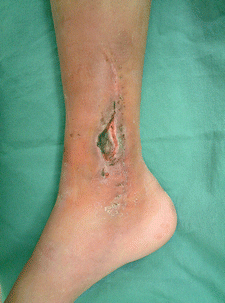

Fig. 16.7

Procedure 1: The osteomyelitis region of the distal area of right medial lower leg is debrided, and sustained release antibiotic hydroxyapatite (Boneceram-P ®) inserted